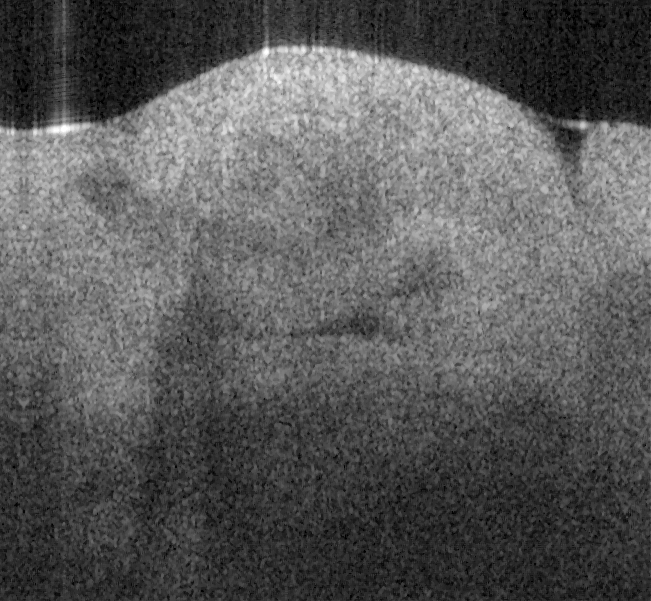

Fig. 18 shows ex vivo images of heart atrium (a, b), artery (c) of mice, and heart atrium (d, e, f)

of pig with forward-view probe with ball lens #16 acquired by our catheter-based complex

SS-OCT using our 3x3 Mach-Zehnder interferometer with unbalanced differential detection

technique with image size of 2x2mm. The shapes and structures of these internal organs of

small and large animals are viewed clearly from these OCT images.